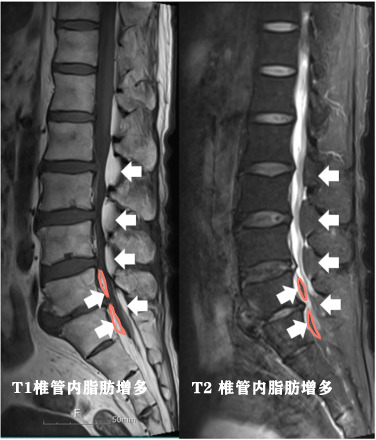

●脂肪瘤也会生长在脊柱内,这种情况以往核磁虽然有了体现,但是由于对这种疾病的认识过浅,往往容易被临床医生和操作医生所忽视,这种情况通常被成为:硬膜外脂肪瘤或特发性硬膜外脂肪增多症,胸椎发生比率较高,占60%,腰椎略少,占40%左右,这种疾病多见于常年使用激素人群和超重人群【2】。

说句题外话,对于这种疾病最开始本人也是没有意识到的,很多遇到的患者存在这种疾病因为没有认识而忽视了,后来也是在文献当中遇到了这种疾病才开始重视起来。之后在门诊遇到了一位父亲,他拿着孩子的腰椎核磁片子来复诊,谈及了这个疾病,为什么做腰椎核磁呢?因为孩子11岁了还是尿床,做了各种检查找不到病因,后来几经转折找到了一位专家,发现了椎管内特别严重的脂肪增多,怀疑椎管内脂肪瘤,手术切除了脂肪瘤以后,孩子的问题消失了。(说实话这次聊天令我很难忘,医生真的有必要时刻拓展自己的医学知识,有的时候一张核磁片子就摆在那里,能不能发现问题是真正的问题!)